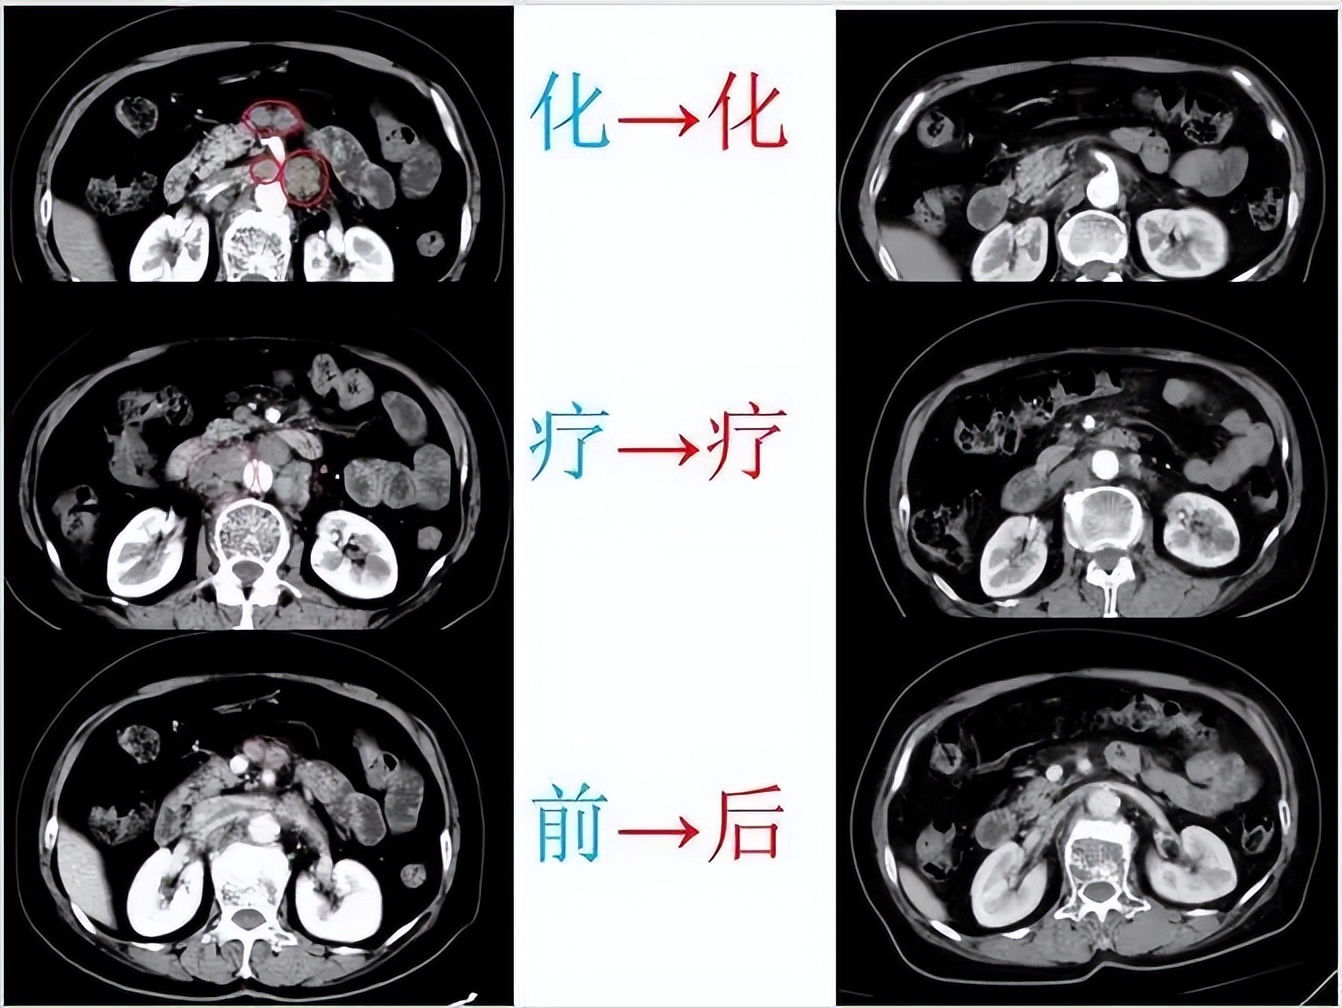

在经过二程化疗后,吴阿姨疼痛明显减轻,肿瘤也有所缩小。综合考虑吴阿姨的身体情况,科室为她制定了新的治疗方案:

经过治疗后,吴阿姨的疼痛得到了控制,体重增加,肿瘤也出现缩小。目前,吴阿姨已停服止痛药,并且自理能力得到了提高。

化疗前后对比